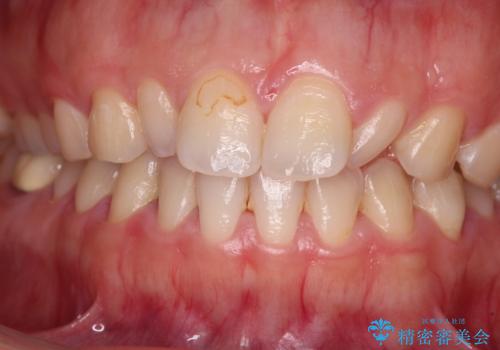

- 前歯の矮小歯と捻れや変色を気にして来院された患者様です。

結婚式が近いということもあり、前歯4本をオールセラミッククラウンにて補綴治療することとしました。